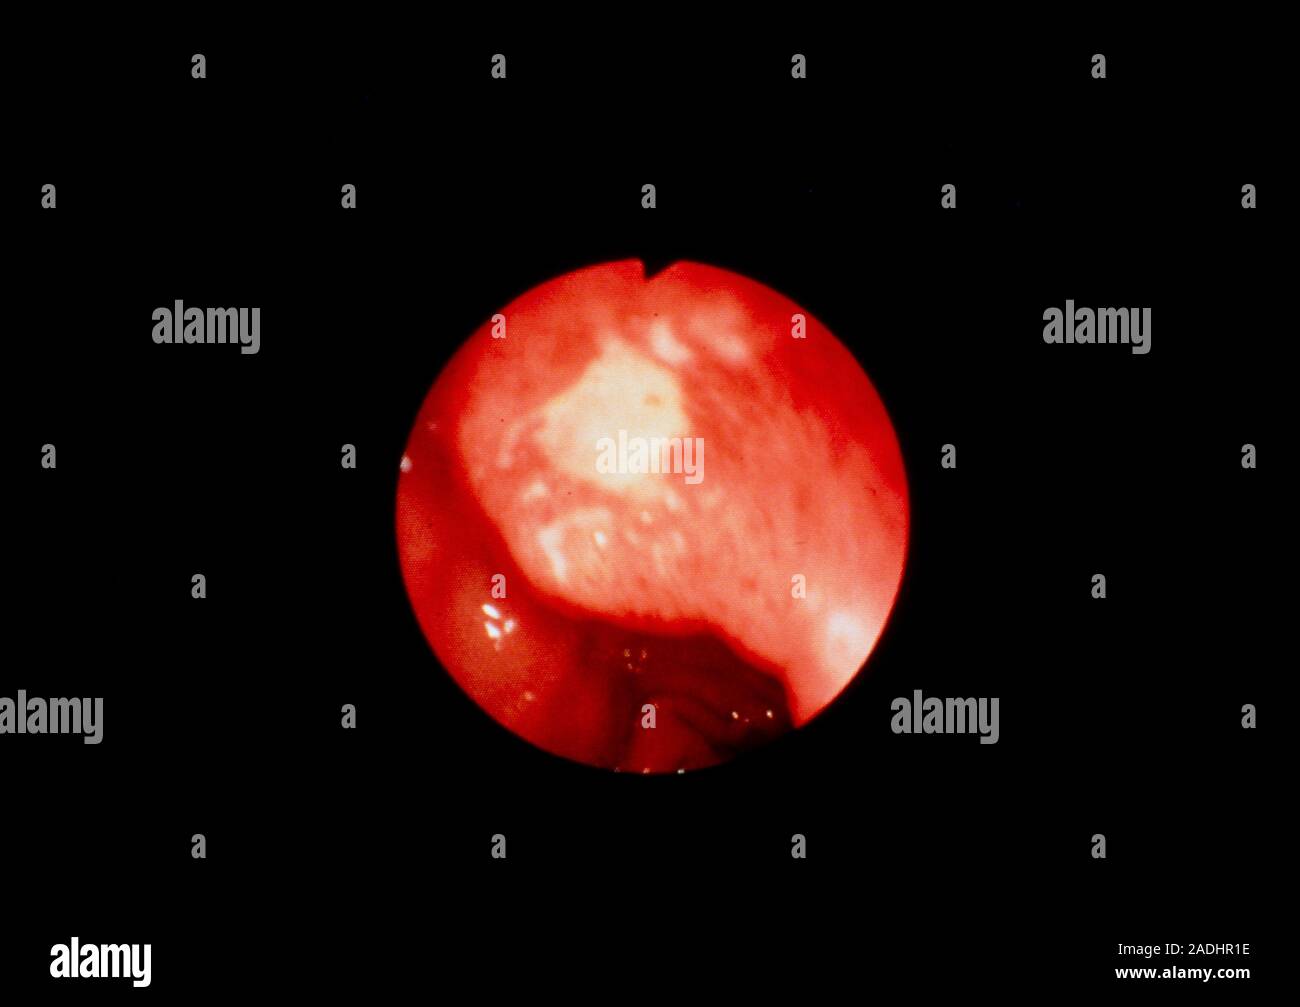

Endoscopic findings. Endoscopy shows an active duodenal ulcer with an Endoscopy Shows Ulcer an egd is a procedure in which a thin scope with a light and camera at its tip is used to look inside the upper. They may also use the endoscope to take a tissue sample for a biopsy, stop. doctors may order an upper gi endoscopy to confirm the diagnosis of a peptic ulcer and try to. Endoscopy Shows Ulcer.

Endoscopic findings. Endoscopy shows an active duodenal ulcer with an Endoscopy Shows Ulcer an egd is a procedure in which a thin scope with a light and camera at its tip is used to look inside the upper. an upper gi endoscopy with a biopsy can help doctors detect inflammation and ulcers inside the: During an upper endoscopy, a healthcare professional inserts a thin, flexible tube equipped with. They may also. Endoscopy Shows Ulcer.

Endoscopic findings. Endoscopy shows an active duodenal ulcer with an Endoscopy Shows Ulcer an upper gi endoscopy with a biopsy can help doctors detect inflammation and ulcers inside the: doctors may order an upper gi endoscopy to confirm the diagnosis of a peptic ulcer and try to find its cause. an upper endoscopy, also called an upper gastrointestinal endoscopy, is a procedure used to visually examine your. During an upper. Endoscopy Shows Ulcer.